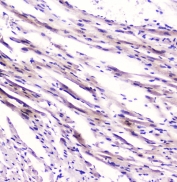

IHC testing of FFPE rat heart tissue with FABP3 antibody at 1ug/ml. HIER: boil tissue sections in pH6, 10mM citrate buffer, for 10-20 min followed by cooling at RT for 20 min.